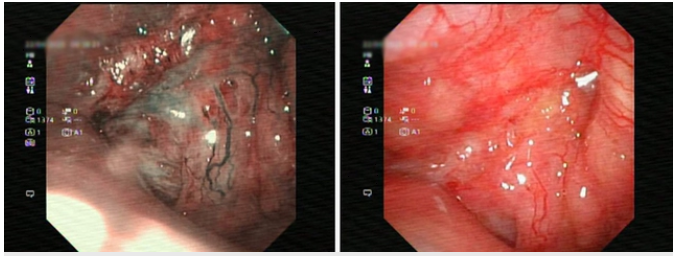

Nội soi phát hiện khối u ở vòm họng. Ảnh: BVCC

Bệnh nhân được thăm khám và thực hiện các thăm dò cần thiết để đánh giá tình trạng sức khoẻ. Hình ảnh cộng hưởng từ (MRI) cho thấy tổn thương thâm nhiễm vùng vòm họng và thành hầu miệng bên phải, xâm lấn xương nền sọ, thành xoang bướm phải và lan đến vùng lỗ mũi sau phải. Ghi nhận thêm một nốt ngấm thuốc tại xương trán phải, cần loại trừ tổn thương ác tính. Đồng thời phát hiện nhiều hạch nhỏ vùng dưới cằm và hai bên góc hàm.

Kết quả giải phẫu bệnh từ mẫu sinh thiết vòm họng xác định đây là ung thư biểu mô vảy không sừng hóa, loại mất biệt hóa – một thể ác tính cao.